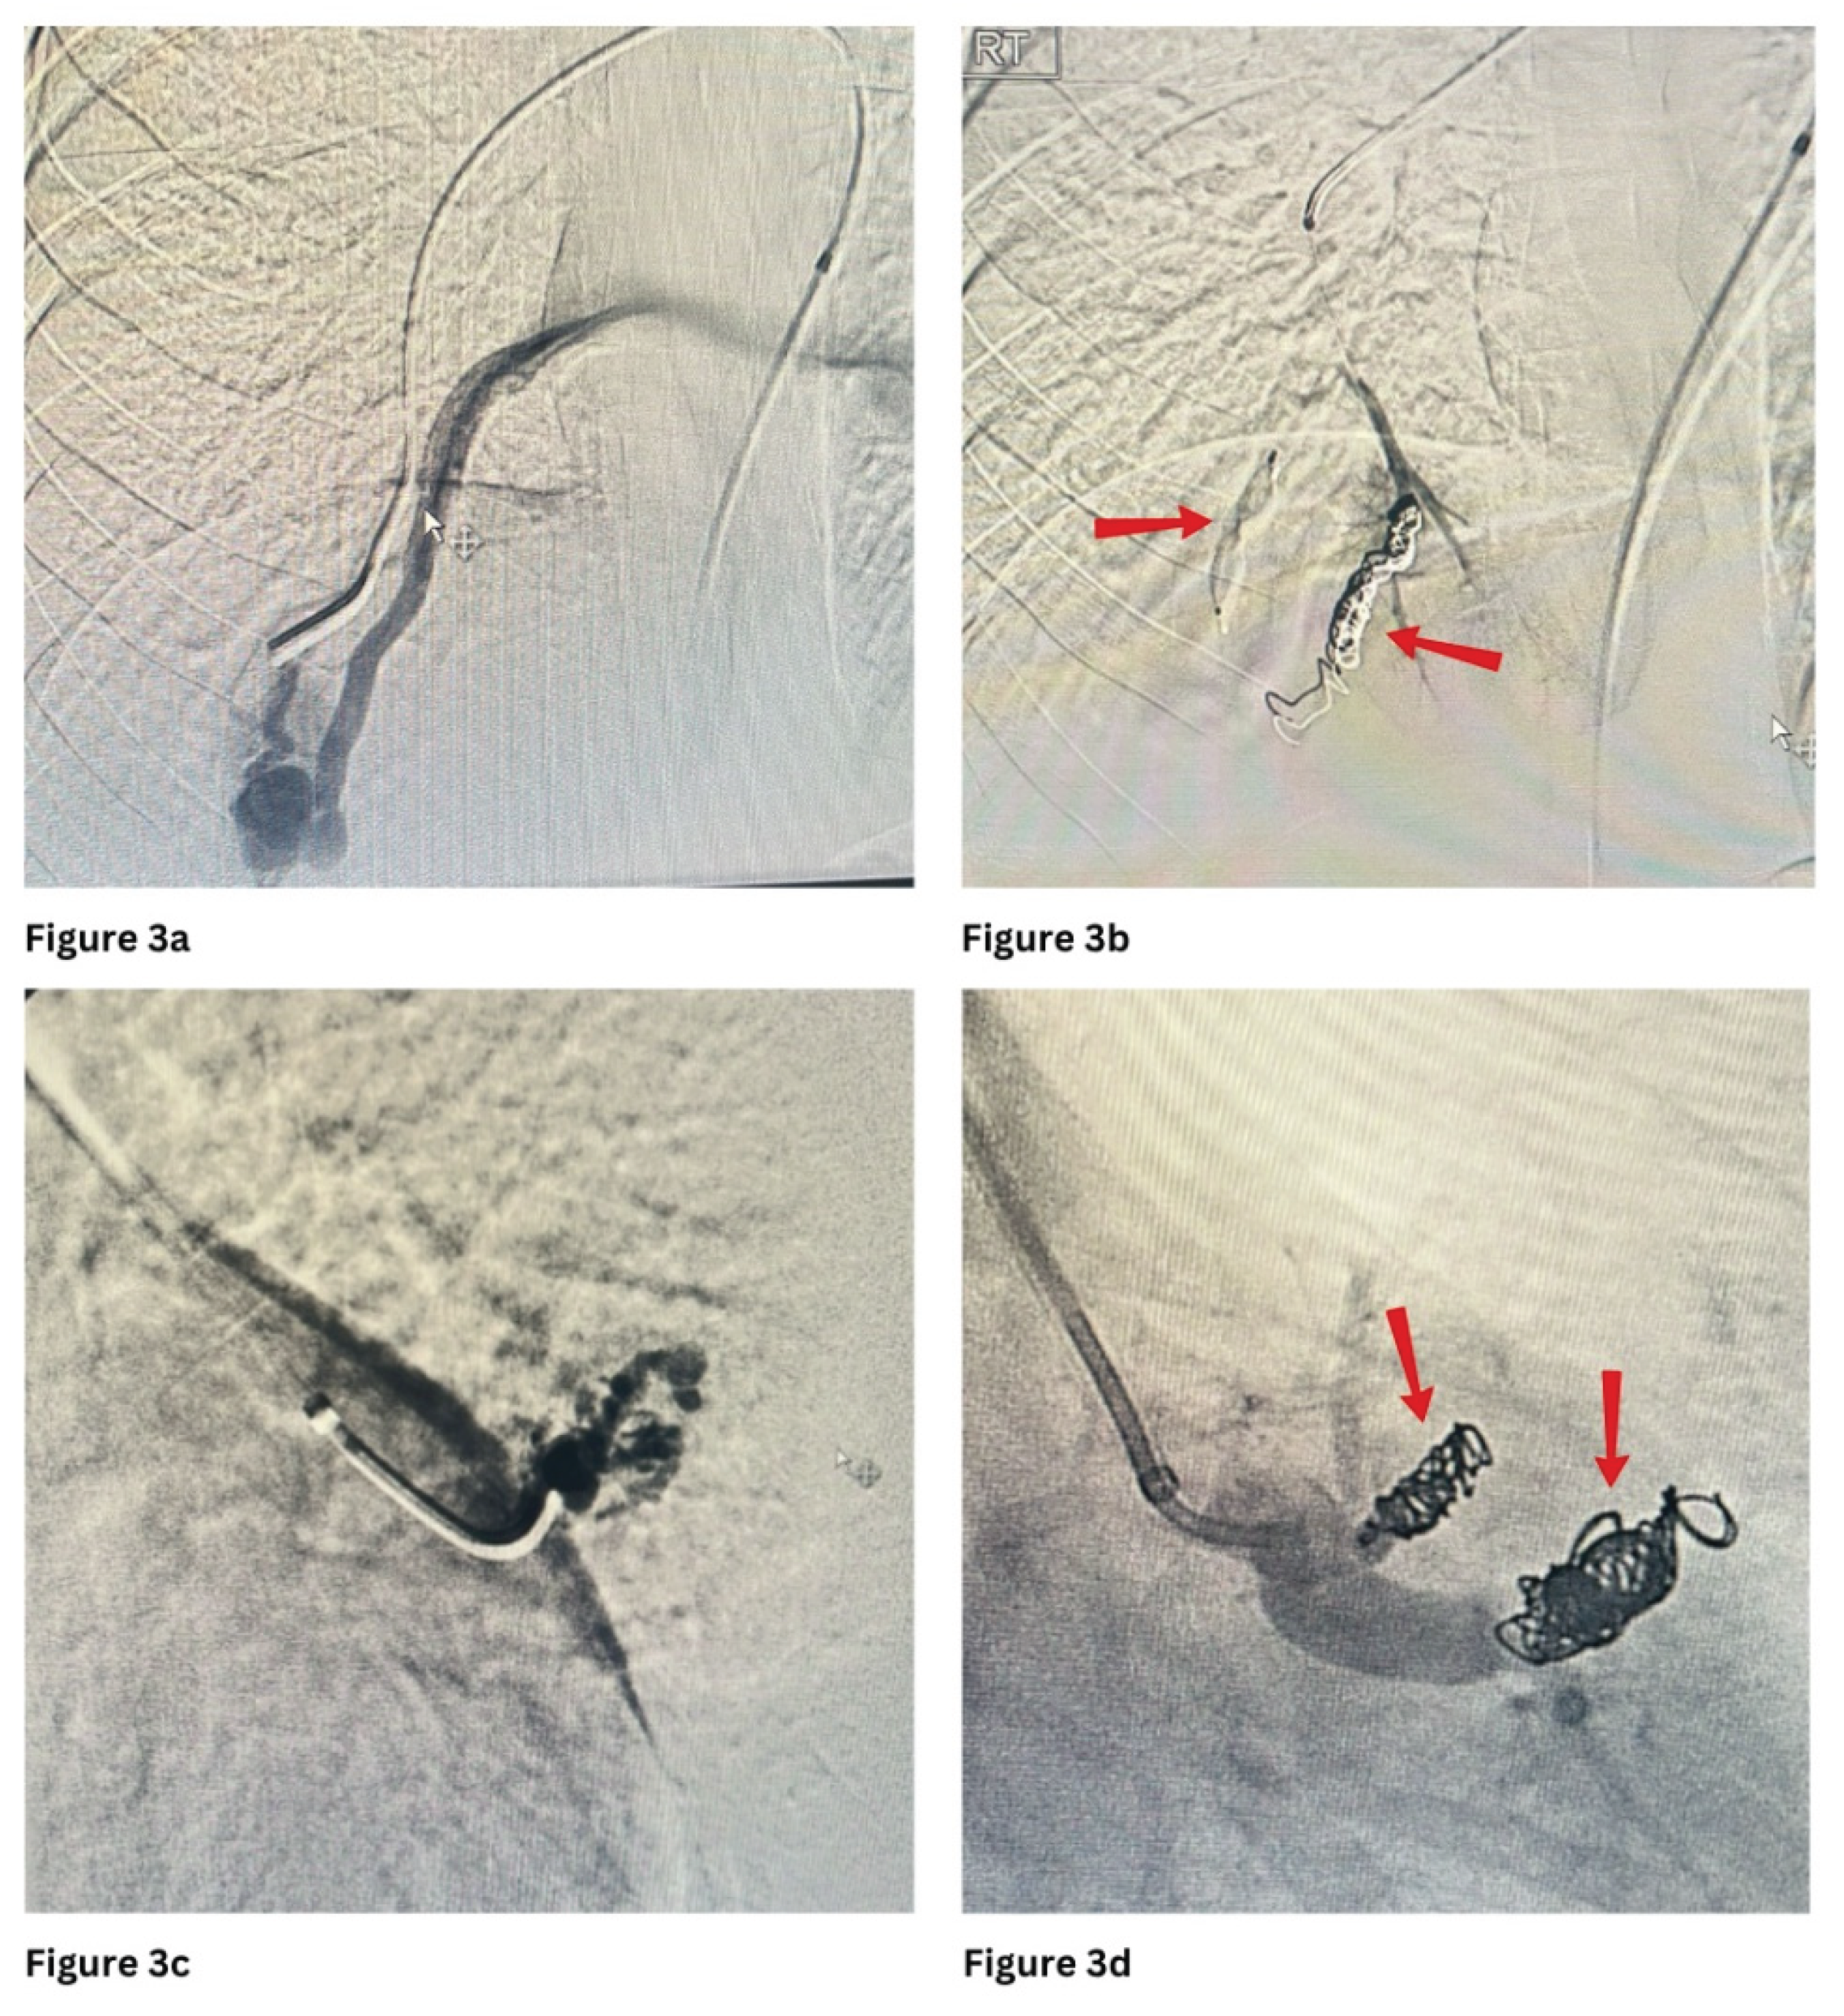

Figure 1 and Figure 3 show PAVMs embolised using detachable coils and/or AVP in simple and complex PAVMs, respectively.

Figure 3. a and b show pre and post embolization of the complex PAVM with an AVP plug and 2 coils at the right lower lobe. c and d show pre and post embolization of the complex PAVM with 3 coils at the left side.